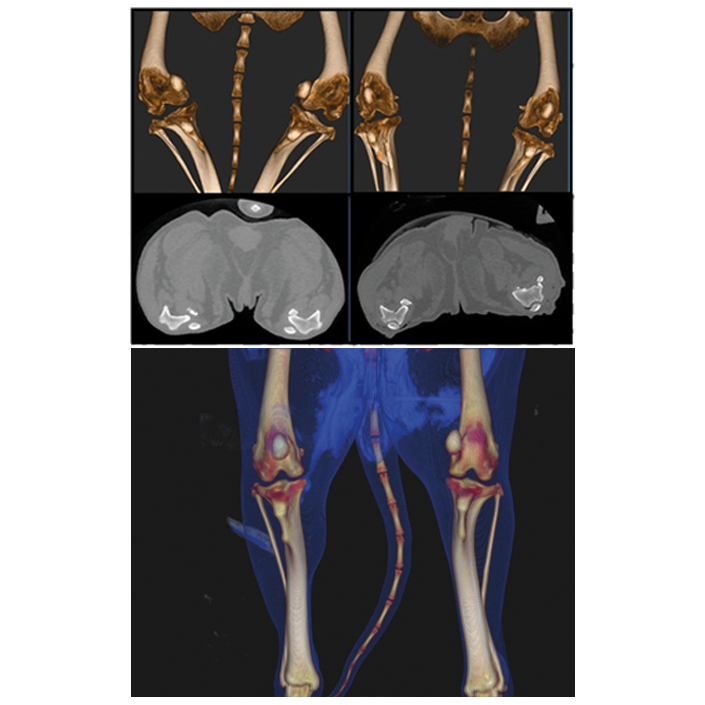

| 3D-Scanzeit | Rekonstruktionszeit | Brennpunkt | Voxelgröße | FOV min | FOV max |

|---|---|---|---|---|---|

| 18 – 36 Sek | < 1 Minute | 0,3 mm | 100 – 300 µm | 6 x 6 cm | 21 x 19 cm |